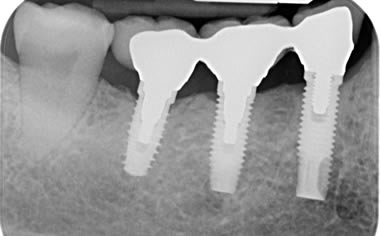

Case One (3 images)

Missing lower teeth replaced by three dental implants and crowns.